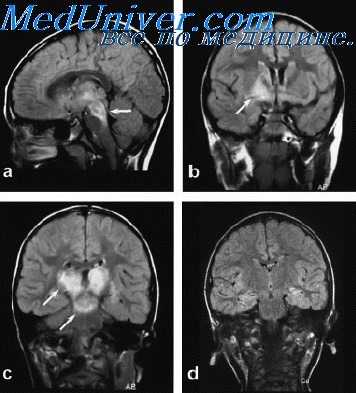

- МРТ головного мозга. Необходима для исключения сопутствующих церебральных поражений: туберкулёза, токсоплазмоза. Смешанная грибково-бактериальная, протозойно-грибковая инфекция встречается у иммунокомпрометированных больных.

- КТ, МРТ головного мозга. Определяется утолщение, уплотнение оболочек мозга, диффузные изменения церебральных тканей. Наличие воспалительных очагов визуализируется не всегда. При паразитарной этиологии характерны округлые очаги гетерогенной структуры с кольцевидным усилением по периферии.